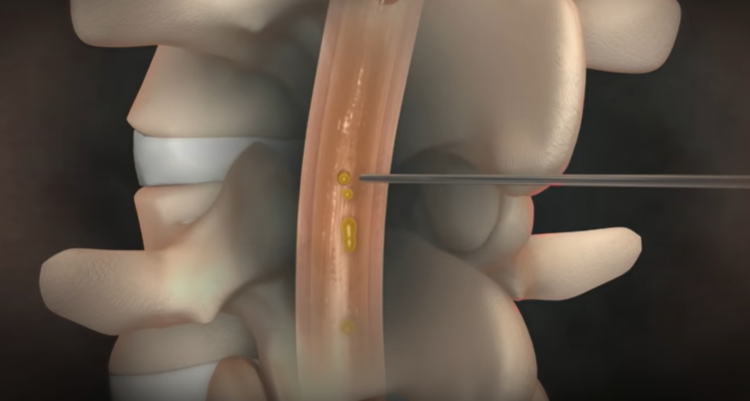

뇌척수액 누출로 인한 두통

뇌척수액이 척추 어디에선가 새어 빠져나가게 되면

그 위에 떠 있던 뇌가 아래로 주저앉으면서 심각한 두통을 유발한다.

물주머니에 뇌가 담겨 있다고 생각하면 된다. 물이 150cc 정도 있는데 그 안에 1.4kg 정도의 뇌가 떠 있다고 보면 된다. 이 무게를 실제 못 느끼는 것은 부력 때문인데, 물 주머니가 새는 경우가 있다. 그러면 물이 빠지면서 부력이 없어지니까, 뇌가 주저앉으면서 심한 두통을 일으킬 수 있는 것이다. 고통지수 10이라고 하면 10점 이상의 도통이라고 할 수 있다. 특징은 서있을 때는 척수액이 빠지기 때문에 굉장한 통증을 유발하는데, 누우면 최대 1분 내로 두통이 없어진다. 그러나 다시 일어나면 척수액이 더 빠지고 뇌가 밑으로 처지면서 극심한 통증이 재발한다.

뇌척수액 누출 두통의 치료

시술은 국소 마취제를 주사한 후에, 가느다란 관인 카테터를 척수를 싸고 있는 격막의 바깥 공간에 삽입하고

그 안으로 환자의 혈액을 주입하면 피가 응고되면서 누수를 막아 준다.

이때 새로 만들어진 뇌척수액이 채워지면서 주저앉았던 뇌가 제자리를 찾아간다.